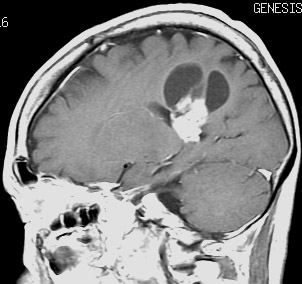

思春期に難治性てんかんで発症した典型例 occult PXA?

7歳児に頭痛に嘔気を伴う,1分間くらいの短い発作で発症しました。

左は8歳時のMRIで,異常所見がありませんでした。左側頭葉に発作時の異常脳波所見が認められ,側頭葉てんかんの診断でカルバマゼピンの投与が開始されました。9歳時に精神症状を呈する発作となりレベチラセタムとゾニザミドが加えられました。右側のMRIは9歳時のものですが異常所見はありませんでした。前後にさまざまな画像が撮影されていましたが脳腫瘍の所見はありませんでした。

11歳時のMRIで側頭葉下面に異常所見が出現しました。

カルバマゼピン,ガバペンチン,ゾニザミド,ラコサミド,クロバザムの5剤投与を受けていましたが発作は制御できませんでした。

12歳時,私のところへ来た時のガドリニウム増強像です。開頭手術で扁桃体を含めて全摘出してから発作は止まり,術後3年で抗てんかん薬は中断できています。